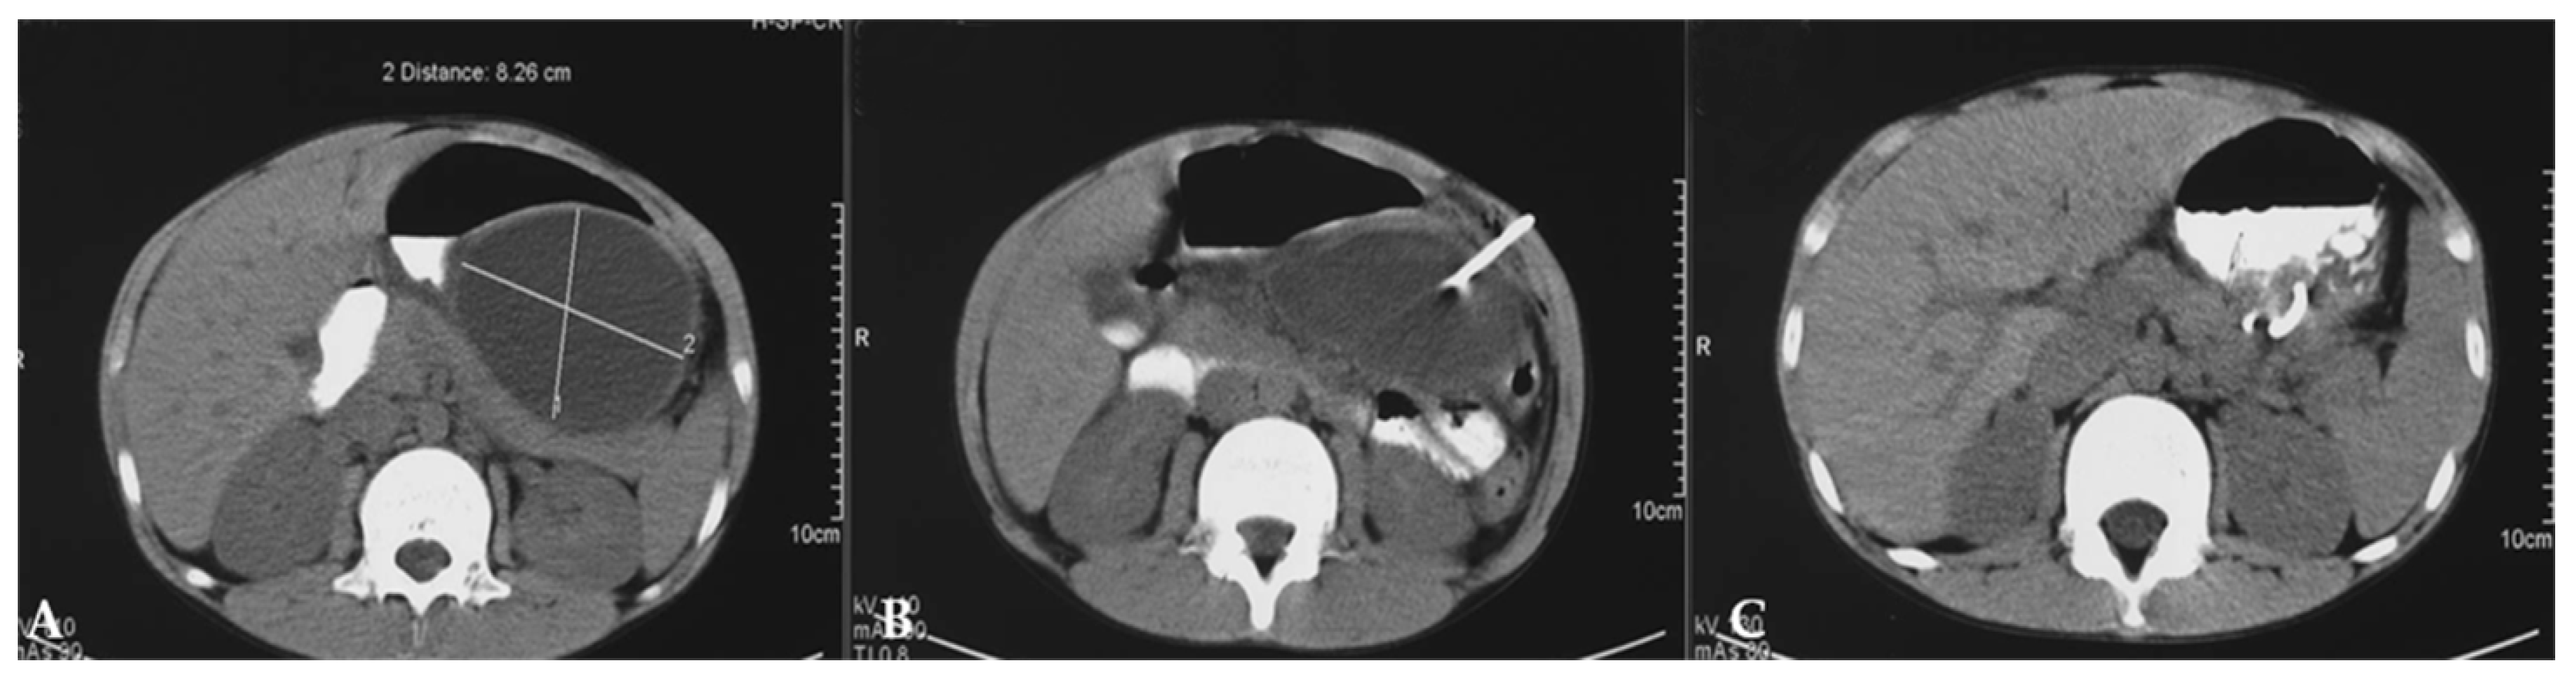

6. Pancreatic Injury

- Naik-Mathuria, B.J.; Rosenfeld, E.H.; Gosain, A.; Burd, R.; Falcone, R.A., Jr.; Thakkar, R.; Gaines, B.; Mooney, D.; Escobar, M.; Jafri, M.; et al. Proposed clinical pathway for nonoperative management of high-grade pediatric pancreatic injuries based on a multicenter analysis: A pediatric trauma society collaborative. J. Trauma Acute Care Surg. 2017, 83, 589–596. [Google Scholar] [CrossRef]

- Rosenfeld, E.H.; Vogel, A.M.; Jafri, M.; Burd, R.; Russell, R.; Beaudin, M.; Sandler, A.; Thakkar, R.; Falcone, R.A., Jr.; Wills, H.; et al. Management and outcomes of peripancreatic fluid collections and pseudocysts following non-operative management of pancreatic injuries in children. Pediatr. Surg. Int. 2019, 35, 861–867. [Google Scholar] [CrossRef]

- Akshintala, V.S.; Saxena, P.; Zaheer, A.; Rana, U.; Hutfless, S.M.; Lennon, A.M.; Canto, M.I.; Kalloo, A.N.; Khashab, M.A.; Singh, V.K. A comparative evaluation of outcomes of endoscopic versus percutaneous drainage for symptomatic pancreatic pseudocysts. Gastrointest. Endosc. 2014, 79, 921–928. [Google Scholar] [CrossRef]

- Patel, P.A.; Gibson, C.; Minhas, K.S.; Stuart, S.; De Coppi, P.; Roebuck, D.J. Pancreatic pseudocyst drainage in children by image-guided cystogastrostomy and stent insertion. Pediatr. Radiol. 2019, 49, 1816–1822. [Google Scholar] [CrossRef]

- Giakoustidis, A.; Antoniadis, N.; Giorgakis, I.; Tsoulfas, G.; Dimitriadis, E.; Giakoustidis, D. Pancreatic pseudocyst in a child due to blunt andominal trauma during a football game. Hippokratia. 2012, 16, 71–73. [Google Scholar]

- Pan, G.; Wan, M.H.; Xie, K.L.; Li, W.; Hu, W.M.; Liu, X.B.; Tang, W.F.; Wu, H. Classification and Management of Pancreatic Pseudocysts. Medicine 2015, 94, e960. [Google Scholar] [CrossRef]